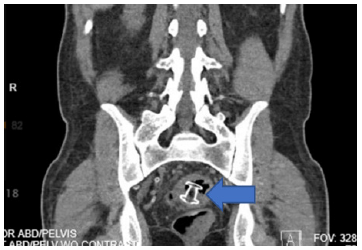

41-year-old male with a history of end stage renal disease secondary to type 1 diabetes on hemodialysis had undergone SPK with enteric drainage. 8 months later, he presented with neutropenic fever, malaise, and diarrhea. He started on IV antibiotics. CT of the abdomen and pelvis revealed a multiloculated, thick-walled, rim-enhancing peri-pancreatic transplant fluid collection in the pelvis with a large intramural recto-sigmoid junction abscess formation that near complete obstruct the lumen of the sigmoid colon (Figures 1,2). The intramural component measured approximately 5.9 x 4.4 x 10.8cm.

Figure 1: CT of peri-pancreas transplant abscess with intraluminal component of the recto-sigmoid junction (Coronal).